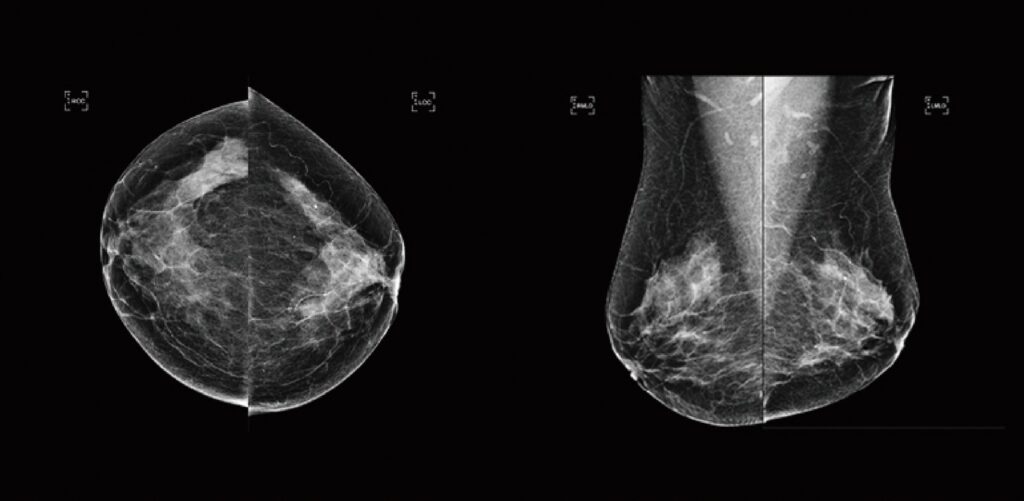

See the SecondReadAI Difference

Radiologist review: no cancer detected.